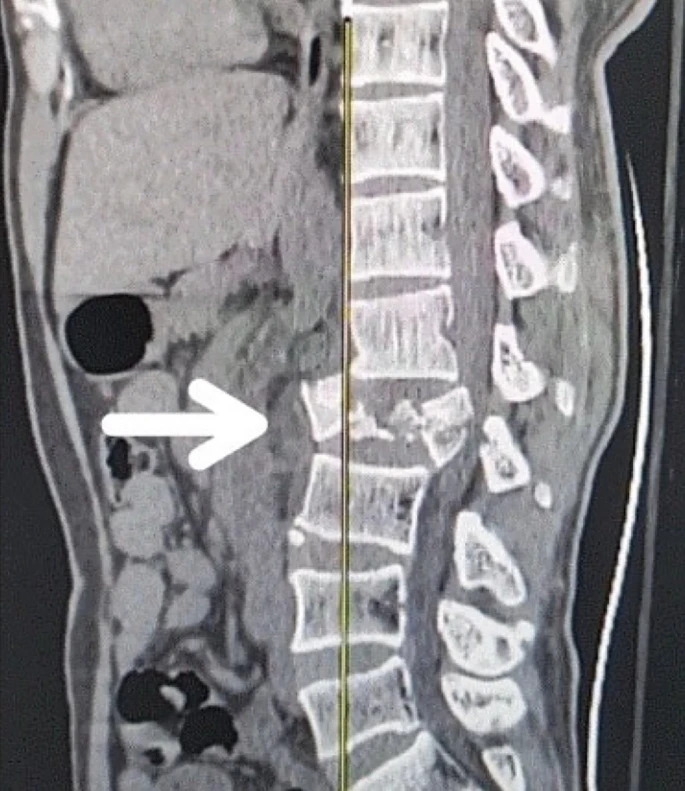

慢性期開(kāi)始于損傷后約3-6個(gè)月,并持續(xù)患者的余生,典型特征是囊腫形成和嚴(yán)重的神經(jīng)膠質(zhì)瘢痕(圖2)。

圖2:X射線(xiàn)圖像顯示慢性期脊髓損傷,通常以囊腫形成為特征,如白色箭頭所示